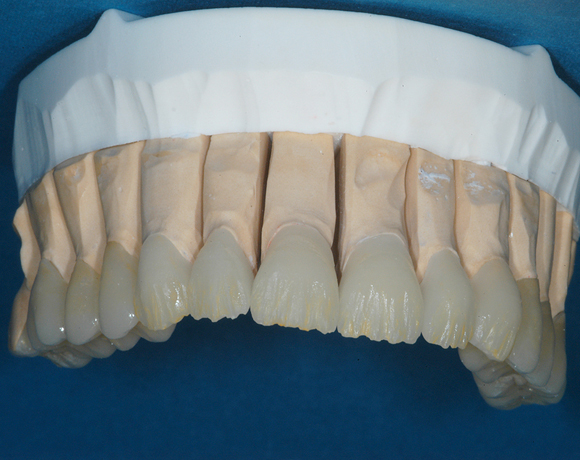

22 Einzelkronen mit Eris for E II

Empress II Presskeramik mit Eris Verblendkeramik bei einer Neuversorgung im Oberkiefer komplett und im Unterkiefer Vollkronen auf den Seitenzähnen.

Ein Projekt aus dem Jahr 2004

Hier wurden der ganze Oberkiefer und die Seitenzähne im Unterkiefer mit neuen Kronen aus Empress 2 und mit Eris Verblendkeramik versorgt.